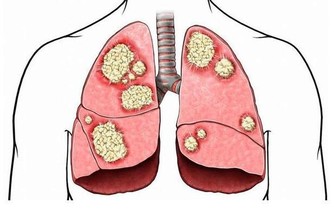

維生素B12的主要生理功能是參與製造骨髓,防止惡性貧血;防止大腦神經受到破壞。維生素B12是B族維生素中迄今為止發現最晚的一種。普通烹調過程損失量約30%。

維生素B12缺乏症是世界上最常見的營養缺乏症之一,特別是在老年人中。維生素B12在保持身體的神經和血細胞健康是非常重要的。因此,當這種維生素水平不足時,身體就會受到影響。

由於其在不同身體過程中的多種用途,當缺乏這種維生素時,人們肯定會遭受痛苦。對於孕婦來說,維生素B12水平低可能意味著神經管缺陷的風險增加。對於其他人,他們可能有患2型糖尿病和其他健康問題的風險。